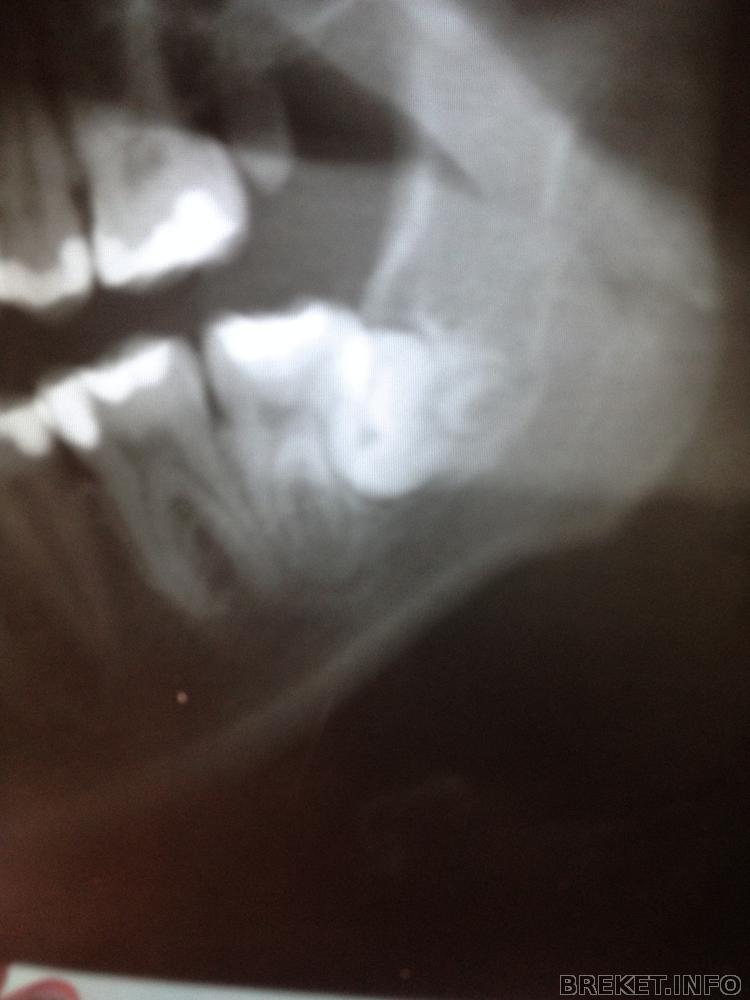

зубки сфотографирую, что бы достать нижнюю 8ку нужно вскрыть слизистую ,причем ее большую часть с вырываемой стороны, это все будет проходить через 7ку, затем нужно выпилить приличный кусок надкостницы , достать эту 8ку не повредив 7ку , ну и потом зашивать, но это все может приобрести обостренный характер...могут быть осложнения..и нервы задеть могут...в общем беда) Спасибо за советы! снимок направлю Андреищеву )

Сочувствую. У вас нижний левый зуб, как у меня верхний правый - растет в 7 так, что надо или сначала 7 удалять потом 8, или разворотить полчелюсти((( Попробуйте обсудить с ортом возможность удаления 5к и стягивания на их место 6 и 7 (в данном случае 8 поспособствуют перемещению этих "тугих" зубов"), тогда и место получите, и 8 может вылезут...

Посмотри на мою восьмерку, она лежала как раз в точно таком же положении, как у тебя (упиралась в 7-ку).

Горизонтальный зуб удалялся конечно посложнее ( можешь подробнее почитать в моем дневнике), но реабилитация, на удивление, проходила легче. 7-ку мне не удаляли и полчелюсти не разворотили))